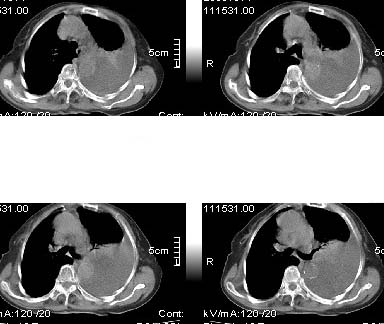

标题: CT4907:[原创]胸部平扫,请讨论!谢谢!!

考虑:左侧大量胸腔积液伴下叶压迫性且不张。

中央型肺癌,下叶不张,胸水

左侧大量胸腔积液伴下叶压迫性且不张,心包积液,左下叶支气管变窄,建议增强扫描,排除占位

左侧大量胸腔积液伴左下肺不张,左侧支气管狭窄,左舌段有膨胀感,中央型肺癌待排,心包有少量液体。肝顶部低密度影,需进一步检查

左侧大量胸腔积液伴左下肺不张,左侧支气管狭窄,左舌段有膨胀感,中央型肺癌待排,心包有少量液体

左侧大量胸腔积液,左下叶受压不张,纵隔向右侧轻移位,虽未见明显骨质破坏,但临床有刺激性咳嗽、胸疼等都支持非善类病变,应穿刺抽液细胞学检查,考虑右肺癌并胸膜转移。肝顶部似有低密度影,可进一步检查,排除转移灶。

患者以抽胸水到上级医院作细胞学检查,肝右顶部的确是{患者以作b超:囊性低密度区,考虑囊肿?}病灶。我的初步意见是考虑是左侧中央型肺癌。

1、高度怀疑:左肺中央型肺癌伴肺不张、胸水;

2、肝上病灶暂考虑囊肿。

3、心包内脂肪影清晰,未见积液。

左侧大量胸腔积液伴左下肺不张,左侧支气管狭窄,左舌段有膨胀感,中央型肺癌待排.